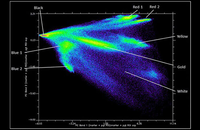

- Tracking of transplanted cells